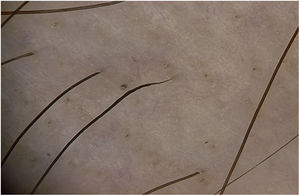

Coudability hairsThe term “coudability hairs” derives from the similarity of the hairs to a coudé catheter. Coudability hairs bend easily when pressure is applied toward the interior of the scalp, leading to a twist in the axis, where damage and narrowing of the hair shaft occur. The proximal end is thinner, and the length is normal. The proximal narrowing of the hair shaft could be due to a rapid anagen-to-catagen transition, thus highlighting a pathological adaptability mechanism. The kinked hairs represent a less severe injury of the hair follicle, which would lead to dystrophic anagen and narrowing of the proximal shaft.25 Couldability hairs have been associated with the inflammatory activity of the disease17,26 and are a pathognomonic sign of AA.17,18